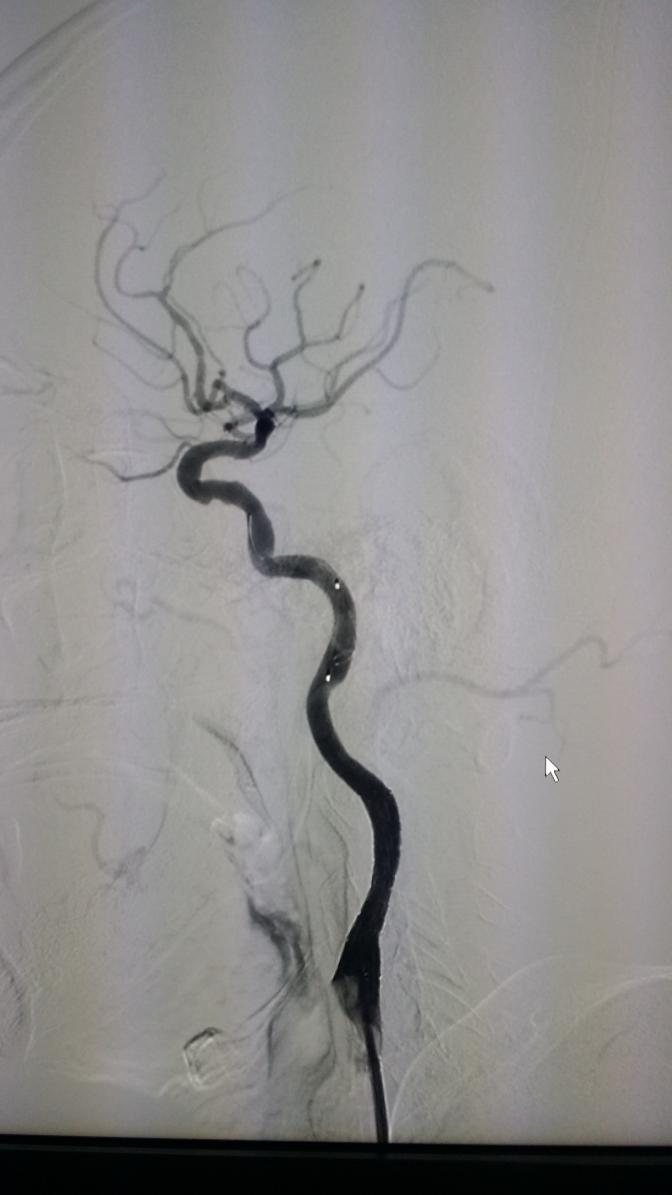

侧位: 术前 支架植入后